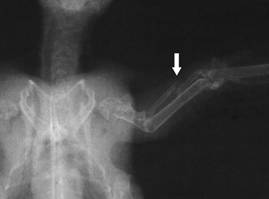

Elbow luxation in

the mediolateral radiation duct: completely torn off

ligament |

the caudocranial radiation duct |